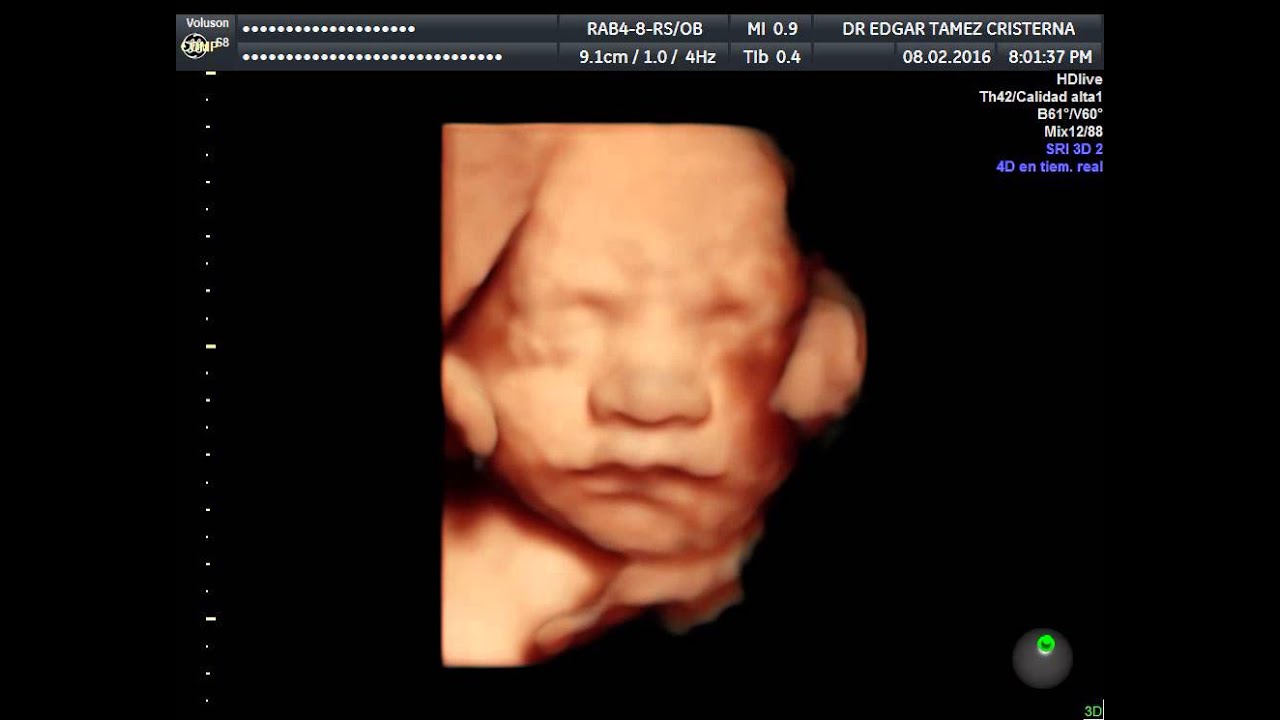

Contamos con el equipo que actualmente ofrece la mejor resolución disponible, tanto para hacer un diagnostico certero, como para que las futuros papás puedan ver una imagen mas realista de su bebe.

Este tipo de ecografía, es la que se hace de manera rutinaria durante el control prenatal, en este estudio se valora el peso del bebe, como esta acomodado, la cantidad de líquido, localización de la placenta, y a partir de las 16 semanas, puede determinarse el sexo fetal con 100% de seguridad No es un estudio muy completo, y por lo que se recomienda realizar el ultrasonido anatomico entre la semana 20-24 para confirmar que el bebe se encuentre bien y descartar la presencia de malformaciones.